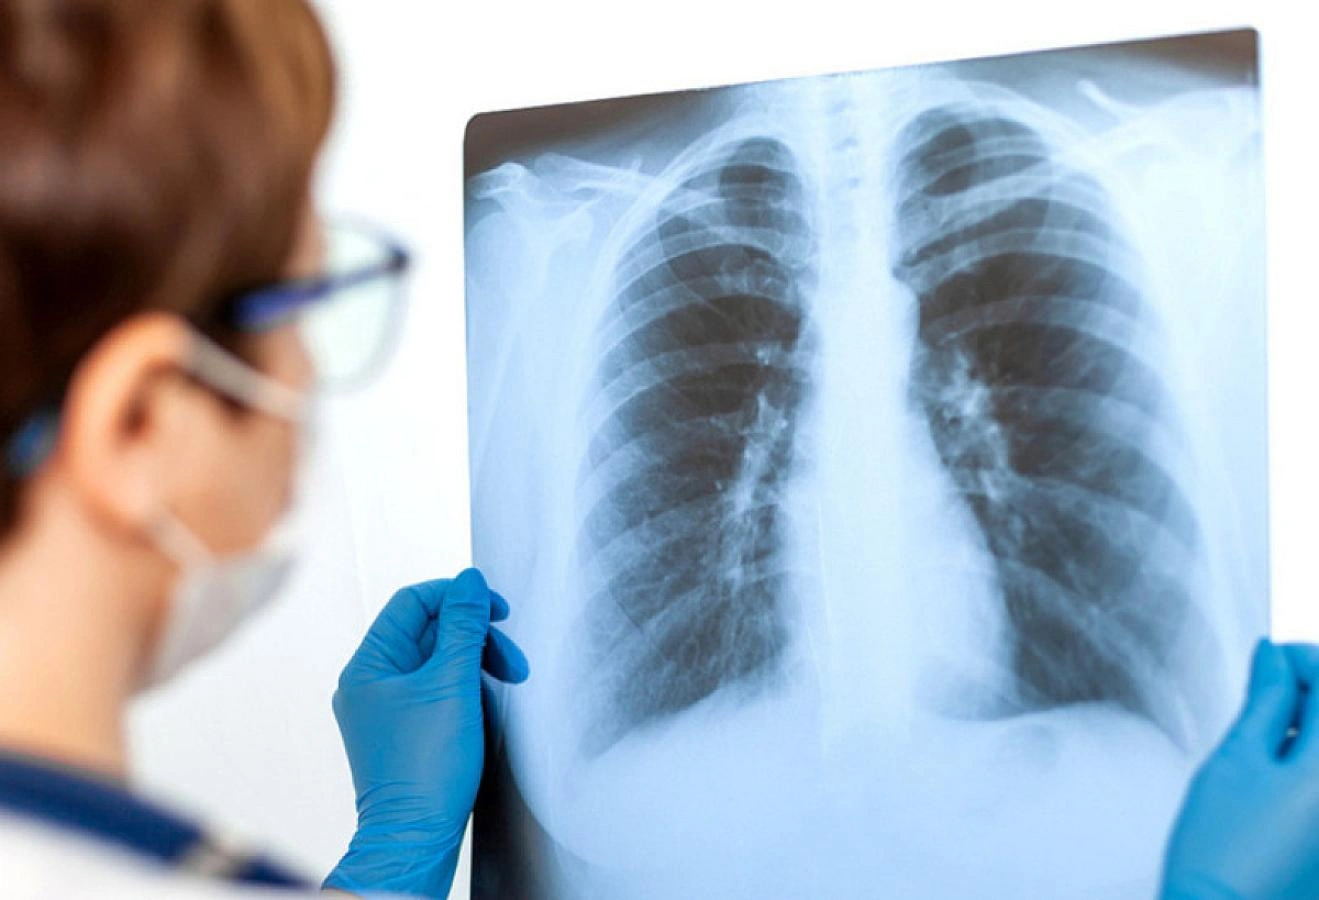

Həkim-infeksionist Əminə İsmixanova Modern.az – a açıqlamasında bildirib ki, pnevmoniya ağciyər toxumasının iltihabi xəstəliyidir. Yüngül, orta və ağır formada keçə bilər və bütün yaş qruplarında rast gəlinir:

“Son zamanlar uşaqlarda daha çox rast gəlindiyi üçün bu haqda daha geniş danışmaq istərdim. Ən riskli yaş qrupları 0–2 yaş (xüsusilə 6 ayadək körpələr), 2–5 yaş və məktəbəqədər dövrlərdir. Lakin biz daha çox pnevmoniya məktəb yaşlı uşaqlarda müşahidə edirik. Buna səbəb kollektiv faktorudur. Uşaqlar sinifdə sıx təmasda olurlar, qapalı məkanda uzun müddət qalırlar və asanlıqla virus, bakteriyalara yoluxurlar. Bu da pnevmoniyanın yayılmasını artırır. Pnevmoniyanın mənşəyi bakterial, viral, atipik və aspirasiondur.

Məktəb yaşlı uşaqlarda məhz atipik daha çox müşahidə olunur. (Mycoplasma pneumoniae,Chlamydia pneumoniae) Bu tip pnevmoniyalar yavaş başlanır. Uzun sürən quru öskürəklə davam edir. Çox vaxt “adi soyuqdəymə” kimi qiymətləndirilir. Nəticədə gec diaqnoz qoyulur və pnevmoniya artıq formalaşmış olur.

Uşaqlarda pnevmoniyanın əsas əlamətləri hərarət (bəzən çox yüksək), sürətli və çətin nəfəsalma, bəzən kürək və sinədə ağrı, davamlı öskürək. halsızlıq, iştahasızlıqdır. Körpələrdə əmmənin azalması, inildəmə müşahidə edilir. Müalicəsi isə səbəbə yönəlik aparılır. Burada əsas onu bilmək lazımdır ki, pnevmoniyaya səbəb tək bakteriyalar deyil, ona görə də antibiotik istifadəsi bu hallarda effekt verməyə bilər".